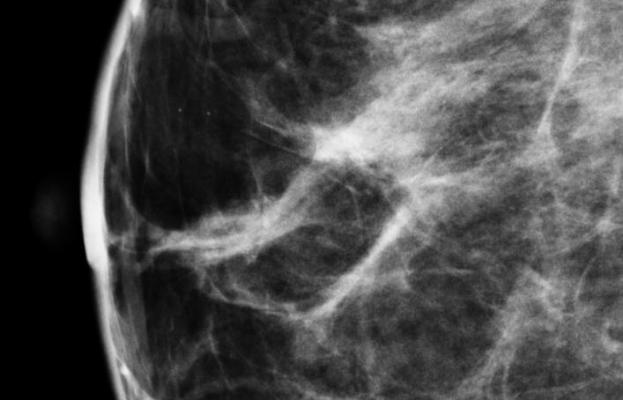

Jung, Dorgan, and colleagues analyzed data from the Dietary Intervention Study in Children (DISC). DISC was a randomized clinical trial initiated in 1988 enrolling 663 children ages 8 to10 years, including 301 girls, that assessed diet on multiple occasions during adolescence. The DISC06 Follow-Up Study, conducted when participants were 25-29 years old, measured breast density by magnetic resonance imaging (MRI) in 177 female DISC participants.

After adjusting for multiple variables, including race, education, adulthood fatness, number of live births, and total energy and protein intakes, the researchers found that higher adolescent intake of saturated fat and lower adolescent intakes of mono- and polyunsaturated fat were associated with higher percent dense breast volume (DBV) in early adulthood.

Women in the highest quartile of saturated fat intake had a mean percent DBV of 21.5 percent compared with 16.4 percent for those in the lowest quartile. A similar difference in percent DBV was found for those in the lowest versus the highest quartile of monounsaturated fat intake.

"The 5 to 6 percentage point difference in percent DBV is relatively modest, compared to the overall distribution of percent DBV observed in our study participants [the 25th percentile and 75th percentile: 9.7 percent to 41.2 percent],"said Jung. "There is no clinical cut-point to define high versus low percent DBV to indicate women at increased risk of breast cancer. However, because there is a gradient of increasing breast cancer risk with increasing breast density, the differences in percent DBV we observed across extreme quartiles in our study, if confirmed, could potentially be of interest with regards to later breast cancer risk.